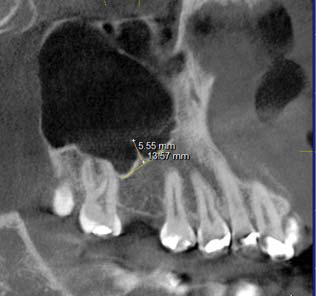

Los septos suelen ser crestas óseas puntiagudas o con forma de arco gótico (6,7,8,9) que se ubican en el seno maxilar, generalmente son hallazgos radiológicos, son de tamaño variable llegando incluso a dividir el seno completamente en dos o más cavidades (1, 2,10-13), su diagnóstico diferencial son las exostosis, sin embargo éstas tienen forma redondeada (6,7,8) (figura 1).

De acuerdo a su origen, existen dos tipos de septos: los primarios y los secundarios. Los primarios o llamados también septos congénitos, se forman durante el desarrollo de la zona central de la cara, originándose de la fusión de residuos durante la formación del seno maxilar (12), (figura 2 y 3); sin embargo Underwood relaciona su origen con las piezas dentarias justificando que se forman por separaciones intermedias del piso antral debido al desarrollo radicular (14). Autores como Lee et al., mencionan que los septos se originan por proyecciones digitales debido a la invaginación del infundíbulo etmoidal durante el desarrollo embrionario donde las paredes adyacentes no se reabsorben (2).

Los septos secundarios, tienen un origen adquirido asociado a atrofia del hueso maxilar como consecuencia de pérdida de dientes, siendo más frecuentes en el piso del seno. La longitud de éstos septos suele ser inferior que los primarios (2,7,12,15,16,17,18). (figura 4 y 5). Gonzales et al., consideraron septos primarios a aquellos donde hay piezas dentarias presentes y los septos secundarios en zonas edéntulas (6).

Se encontraron 298 (65,1%) septos unilaterales y 160 (34,9%) bilaterales (tabla 3); considerando lado, la frecuencia de septos predominó en el lado derecho con 234 y el lado izquierdo presentó un total de 224 septos (tabla 4). La longitud promedio de septos congénitos fue de 5,8mm y para otros septos fue de 5.6mm. El valor p fue igual a 0,523 lo que indica que no hay diferencias estadísticamente significativas entre ambos grupos (tabla 5).